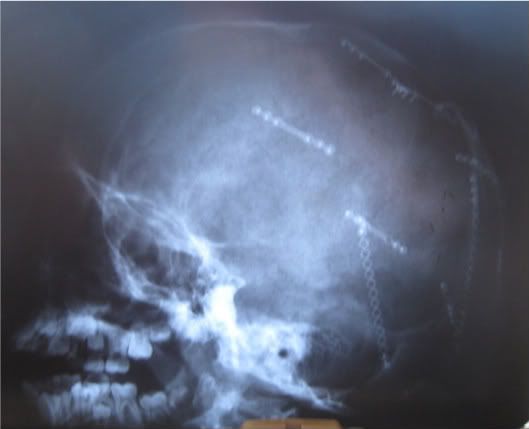

Here's the xrays. These were taken when he was 9 years old so the bone has grown over many of the 'plates' and screws.

ETA: I'm not sure if this is the right way to link to the picture I want to share...BEFORE YOU LOOK READ THIS WARNING: This is a bloody picture of the inside of Robert's skull taken during surgery to show the placement of the screws and plates: -- OK If you're ready click here